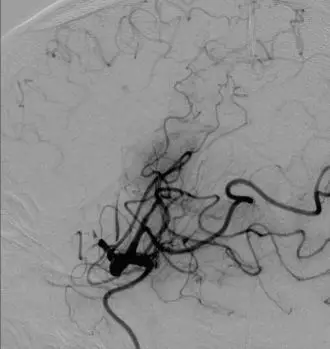

影像学表现与临床症状不匹配,发病超7小时。 DSA: 右侧颈内动脉C1段闭塞;右侧大脑中动脉M1段闭塞,颈外动脉经眼动脉向颅内代偿。

前交通动脉开放,同侧大脑前动脉通过软脑膜支代偿右侧大脑中动脉供血区域。

后循环通过软脑膜支及后交通动脉部分代偿右侧大脑中动脉供血区。